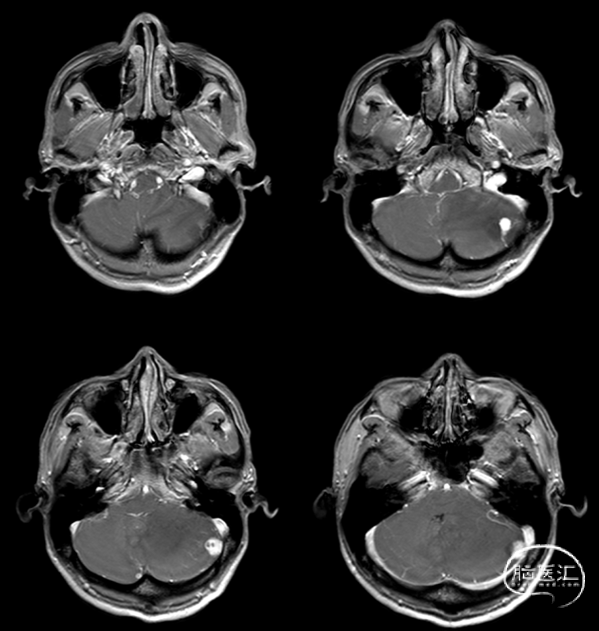

术后CT: